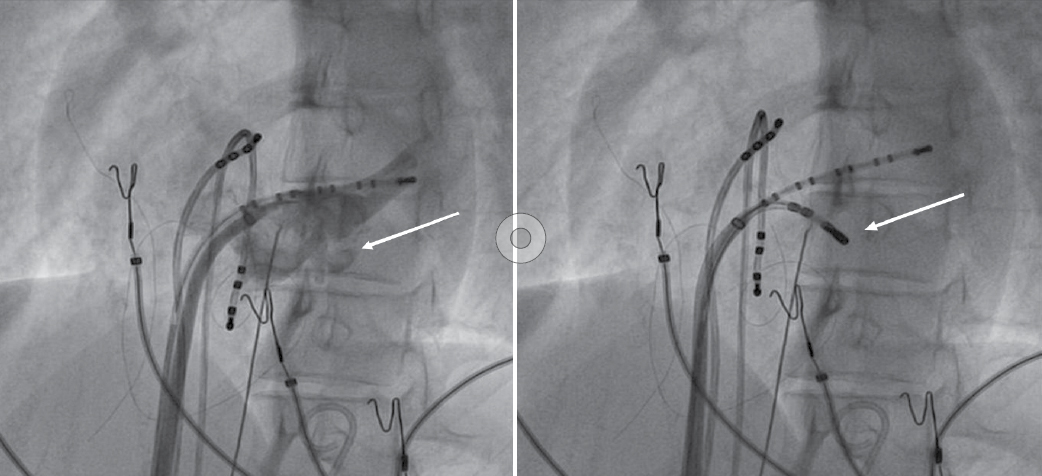

Later on, during programmed atrial stimulation with burst pacing, patient developed another broad complex tachycardia (TCL = 220 ms) with 1:1 AV relationship. The tachycardia was hemodynamically unstable and led to ventricular fibrillation and required direct current cardioversion (DCCV) with 200J (Fig. 4). With the help of steerable ablation catheter, earliest atrial activation during ventricular pacing and earliest ventricular signal in sinus rhythm was mapped at the septal tricuspid annulus (RA mapping) and septal mitral annulus (LA mapping). Afterwards coronary sinus angiogram was taken, which showed a coronary sinus diverticulum near the decapolar coronary sinus 5-6 electrodes (Fig. 5). Radiofrequency applications were delivered at the neck of diverticulum that leads to disappearance of pre-excitation (Fig. 6). Afterwards aggressive programmed stimulation done on and off with isoproterenol that did not induce any atrial arrhythmias.

Figure 5. Coronary sinus angiogram (left) showing coronary sinus diverticulum and site of successful ablation (right).